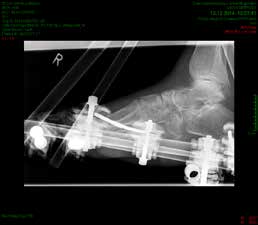

So erhielt ein 67-jähriger männlicher Patient nach operativer Versorgung mittels Fixateur externe neben einer Entlastung nur eine di_CAP-Therapie. Als Hauptdiagnose wurde eine sekundäre Fußfehlstellung in Pes-cavovarus-Position mit chronischem Ulcus am rechten Fußrand bei diabetischer Neuroosteoarthropathie festgehalten (Abb. 2); relevante Nebendiagnosen waren eine pAVK und diabetische Nephropathie. Als operative Therapie wurde eine Stellungskorrektur mit dem Hoffmannschen Fixateur externe durchgeführt (Abb. 3). Intraoperativ konnte eine bakterielle Besiedlung mit Escherichia coli, Enterococcus faecalis und Enterobacter cloacae nachgewiesen werden. Während des stationären Aufenthaltes wurde der Patient zweimal wöchentlich mit di_CAP behandelt. Nach seiner Entlassung erfolgte die Einbestellung zur di_CAP-Therapie nach der 4., 6. und 10. postoperativen Woche. Dabei wurde vor jeder Wundbehandlung ein Abstrich für eine mikrobiologische Untersuchung genommen. Im Verlauf kam es zu einer guten Wundheilung des anfänglich 3 × 5 cm messenden plantaren Ulcus, und in der 10. postoperativen Woche ließ sich eine fast vollkommene Wundheilung beobachten (Abb. 4). Ab der 1. postoperativen Woche war in den mikrobiologischen Abstrichen nur noch E. faecalis nachweisbar, und ab der 4. Woche konnte im Ulcus kein Keim mehr nachgewiesen werden. Aufgrund der geringen Patientenanzahl und der unregelmäßigen Wiedervorstellungen der Patienten konnte die Kohorte nicht suffizient im Verlauf beobachtet werden, um genügend Daten für eine prospektive Studie zu generieren. Die klinischen Erfahrungen der Verfasser decken sich jedoch mit Ergebnissen bisheriger Arbeiten zur di_CAP-Therapie.